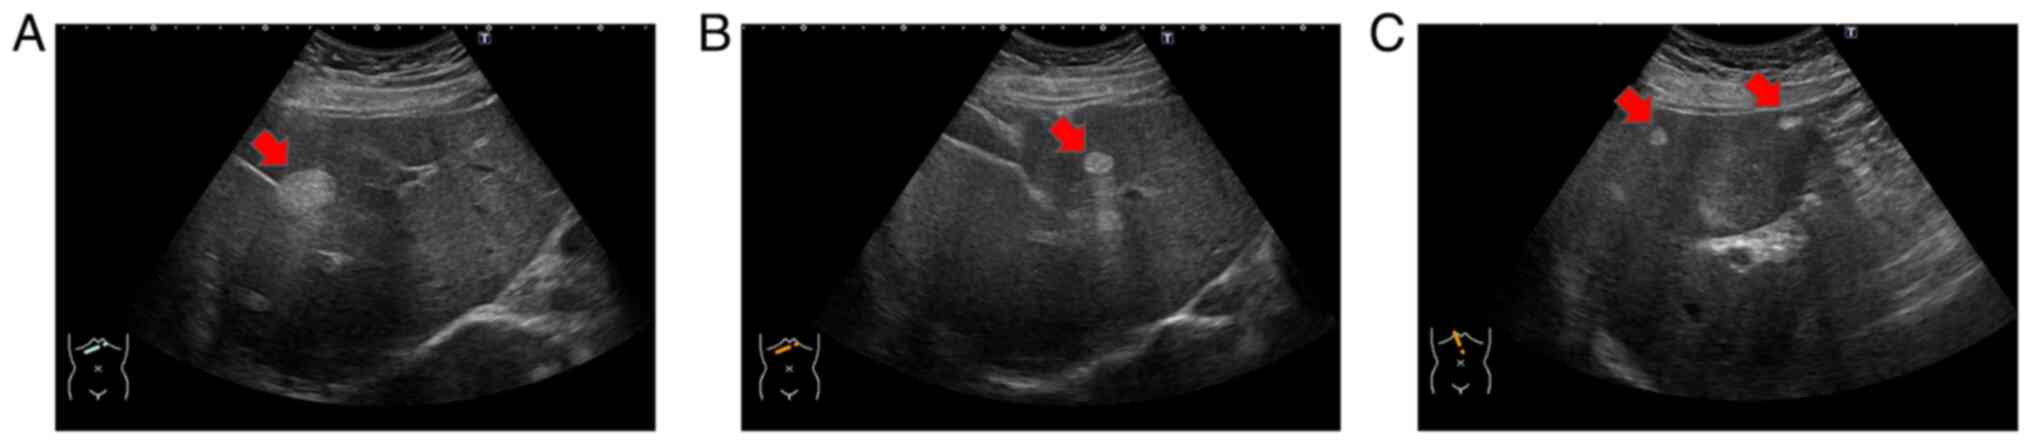

Ultrasonography revealed multiple hyperechoic tumors in the liver (Fig. 1A-C). Magnetic resonance imaging (MRI) was performed before a dynamic computed tomography (CT) scan to limit radiation exposure (8,12). MRI examinations were performed using 1.5-T MR systems (MAGNETOM Sola, Siemens Medical Solutions, Erlangen, Germany). The gradient strengths were 45mT/m with a slew rate of 200T/m/second. Eighteen-element phased array matrix coil was used for signal reception. MRI showed that the main tumor in segment (S)8 had low signal intensity on both T1- and T2-weighted images and slightly high signal intensity on diffusion-weighted imaging (Fig. 2A-C). Contrast-enhanced MRI revealed that the S8 tumor was enhanced in a ring shape during the early contrast phase (Fig. 2D). In the hepatobiliary phase, the periphery had a high signal intensity and the interior had a low signal intensity (Fig. 2E). Near the main tumor in S8, two small tumors were heavily contrasted in the early phase but were not identified in the hepatobiliary phase (Fig. 3). Numerous tumors suspected to be lipomas, focal nodular hyperplasia or arterio-portal shunts were also observed in the liver.

Figure 1

Ultrasonography showed multiple hyperechoic tumors in the liver. (A) 30 and (B) 18-mm hyperechoic lesion was detected near the gallbladder (arrow). (C) Multiple hyperechoic lesions were detected in the right lobe of the liver (arrows).